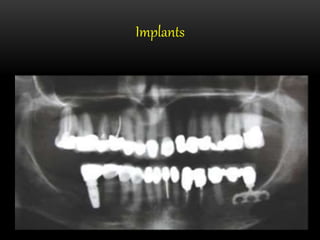

Implants